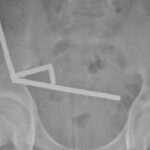

Doctors told her she had basal cell carcinoma, the most common type of skin cancer. Hamilton believes her years of using sunbeds during her pop star days might be to blame.